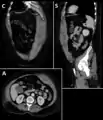

A rectus sheath hematoma is an accumulation of blood in the sheath of the rectus abdominis muscle. It causes abdominal pain with or without a mass.

The hematoma may be caused by either rupture of the epigastric artery or by a muscular tear. Several factors have been identified as predisposing risks for rectus sheath hematoma, including coughing, straining, exercise, hypertension, obesity, previous abdominal surgery, subcutaneous injection, trauma and anticoagulant therapy. With an ageing population and the widespread use of anticoagulant medications, there is evidence that this historically benign condition is becoming more common and more serious.[1] Anticoagulant therapy is used to treat many diseases. However, in the COVID-19 pandemic, anticoagulant therapy was frequently used and therefore the incidence of rectus sheat hematoma increased. [2][3] Given that thrombotic events have been documented in numerous studies, it is advisable to initiate prophylactic and anticoagulant treatment during the early phase of COVID-19 disease. [4]